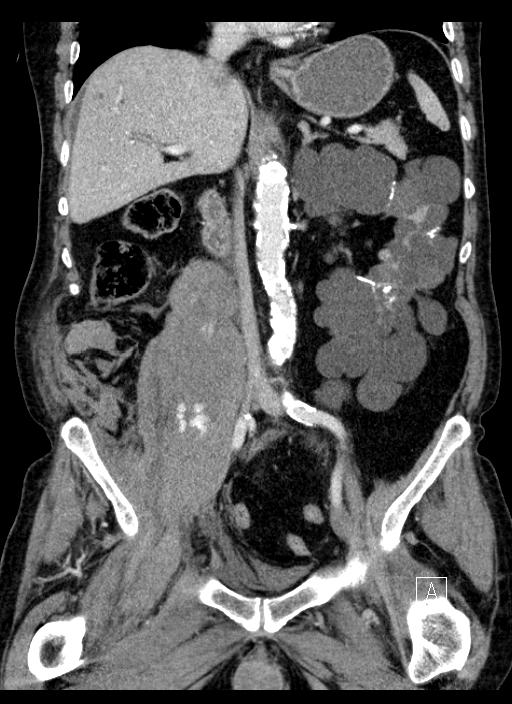

Jobb alhasi fájdalmas resistentia kivizsgálása történt:

Jobb oldalon a  m. psoas maior területén nagy bevérzés látszik, melyen belül egy folyadék-folyadék nívó határon artériás fázisban jelzett mennyiségű, vénás fázisban egyértelműen kivehető kontrasztanyag extravasatio látszik. Aktív vérzés.